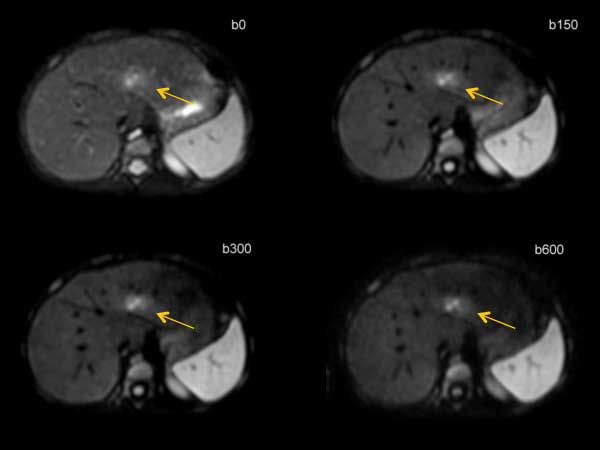

Axial Diffusion (with Resp. Triggering)